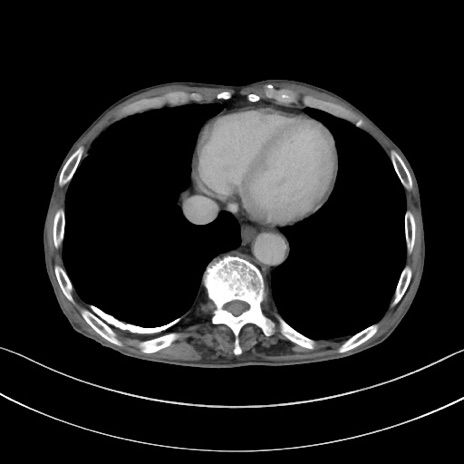

冠状断像

矢状断像